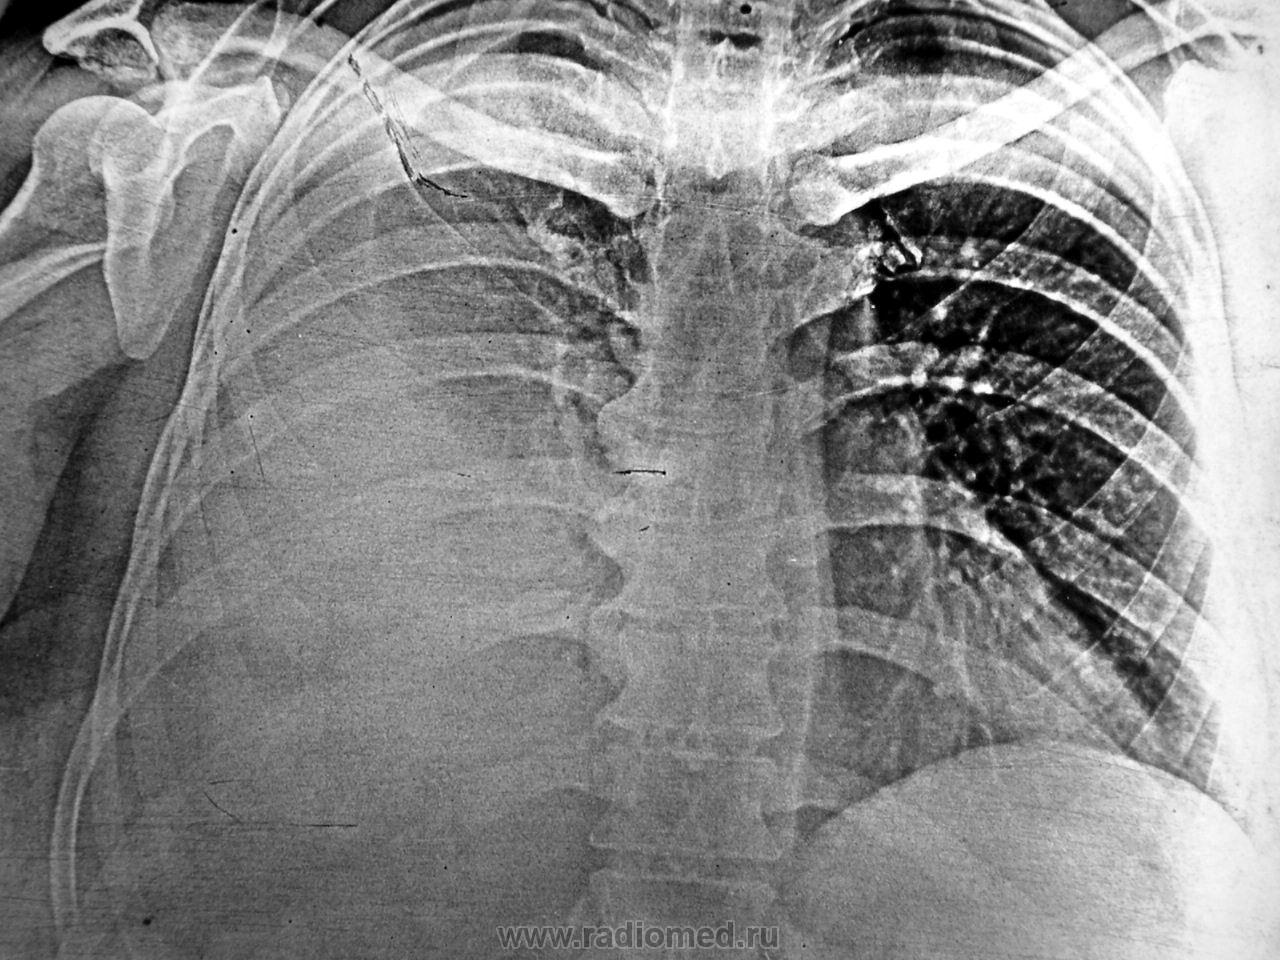

Попробуйте по рентгенологической картине высказаться об этиологии плеврита в каждом наблюдении.

На первой рентгенограмме плеврит вероятно туберкулезной этиологии. Т.к. в левом легком множество мелких очагов. Как мне кажется у них высокая плотность. Хотя такие рентгенограммы вижу впервые. Непривычно. Поэтому не исключаю и онкологическое заболевание.

Нет. Это не очаги в левом лёгком. Это особенности "краевого эффекта", который имеет место быть на электрорентгенограммах.

На правом снимке смущает плохая дифференциация, а местами и отсутствие таковой 10 ребра. "Газовый пузырь желудка" совсем не дифференцируется. Кажется мне, что и с некоторыми грудными позвонками - "кашка". Рискну предположить наличие на правом изображении  параканкрозного выпота.

По всей видимости, "на правом снимке", наряду с выпотом, можно предположить наличие ателектазированной нижней доли правого лёгкого, ибо при наличии такого количества выпота справа, средостение ведет себя довольно прилично, находится там, где положено.

Если есть распространенная диссеминация  - она лучше всего видна за сердцем в виде "пятен"

На левом изображении средостение явно смещено влево.

Вот, что-то, правый главный бронх, мерещится мне обрубанным.

На правом снимке вверху есть плевральное окно, на левом его нет - там намного больше жидкости. Мне легко, я знаю цитологию и анамнез. Справа - год назад удалена молочная железа. Слева - клиника пневмонии.

"Левый снимок" - обрубок правого главного бронха.

В левом случае - цитология - злокачественные клетки - выставлен диагноз мета поражения, ушла к онкологам.

Правый снимок -плеврит воспалительной природы, пневмония, благополучный исход